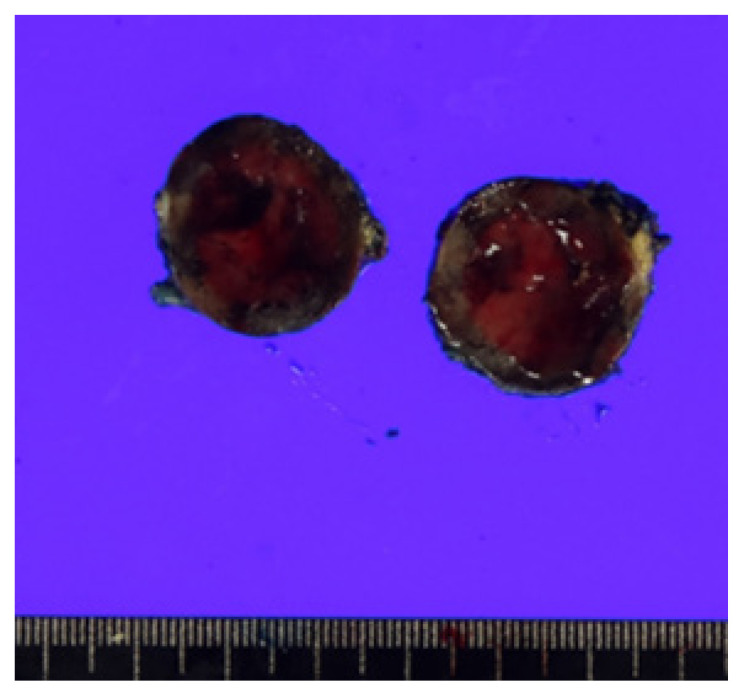

众所周知,分化良好的甲状腺癌(WDTC)会向骨和肺进行远处转移,而腹腔内和肠系膜转移则非常罕见。在此,我们报告了一例WDTC腹腔内肠系膜转移病例。一名 62 岁的男性因患滤泡性甲状腺癌接受了甲状腺叶切除术。一年后发现肺转移。患者同时接受了肺楔形切除术和甲状腺全切除术。11年后,患者血清甲状腺球蛋白水平升高。在检查中发现了肺部转移灶和肠系膜肿块。手术切除了肺部和肠系膜的两个病灶。肠系膜肿块经病理诊断为转移性 WDTC。

Distant metastases of well-differentiated thyroid cancers (WDTCs) to bone and lungs are well known, while intra-abdominal, mesenteric metastases are very rare. Herein, we report a case of intra-abdominal, mesenteric metastasis of WDTC. A 62-year-old man underwent thyroid lobectomy for follicular thyroid cancer. One year later, lung metastasis was observed. The patient simultaneously underwent lung wedge resection and complete thyroidectomy. Eleven years later, serum thyroglobulin level was elevated. On the work-up study, a metastatic lesion in the lungs and a mass in the mesentery were identified. Two lesions of the lung and mesentery were surgically resected. The mass in the mesentery was pathologically diagnosed as metastatic WDTC.